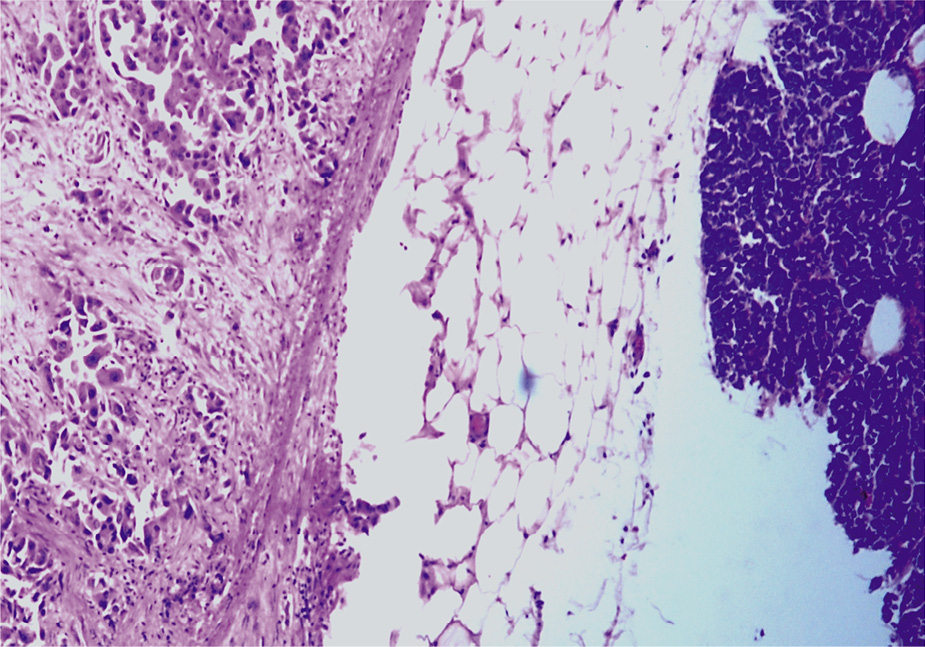

При секционном исследовании определяются признаки, характерные для периферического рака правого легкого с множественными метастазами по всем полям легких, в печень, селезенку, поджелудочную железу, с отсутствием метастазов в лимфатические узлы. При макроскопическом исследовании структура легких просматривается с трудом из-за выраженного диссеминированного наличия серых плотноватых узлов в диаметре от 0,2 до 0,9 см, местами сливающихся. В области средней доли правого легкого определяется опухолевая ткань с выраженным слиянием и тенденцией формирования конгломерата, распространяясь к долевому бронху, без сужения просвета. При гистологическом исследовании отмечаются обширные участки формирования опухолевой ткани, состоящей из солидных структур с железистой дифференцировкой опухолевой ткани разной величины и формы, выстланные крупными приз- матическими клетками с округлыми и овальными базально расположенными ядрами, цитоплазма которых хорошо выражена. Отмечается выраженный полиморфизм клеток с большим числом патологических митозов (рис. 1, 2). В просвете сегментарных и мелких ветвей легочной артерии – свертки крови, тромбы в диаметре от 0,2 до 0,7 см, длиной до 3,0 см, выдавливающиеся в виде «червячков» (рис. 3).

Рис. 3. Микроскопическая картина обтурирующего тромба: просвет сосуда обтурирован массами, состоящими из переплетающихся балок фибрина и эритроцитов, большая часть которых гемолизирована. Окраска гематоксилином и эозином, ×400.